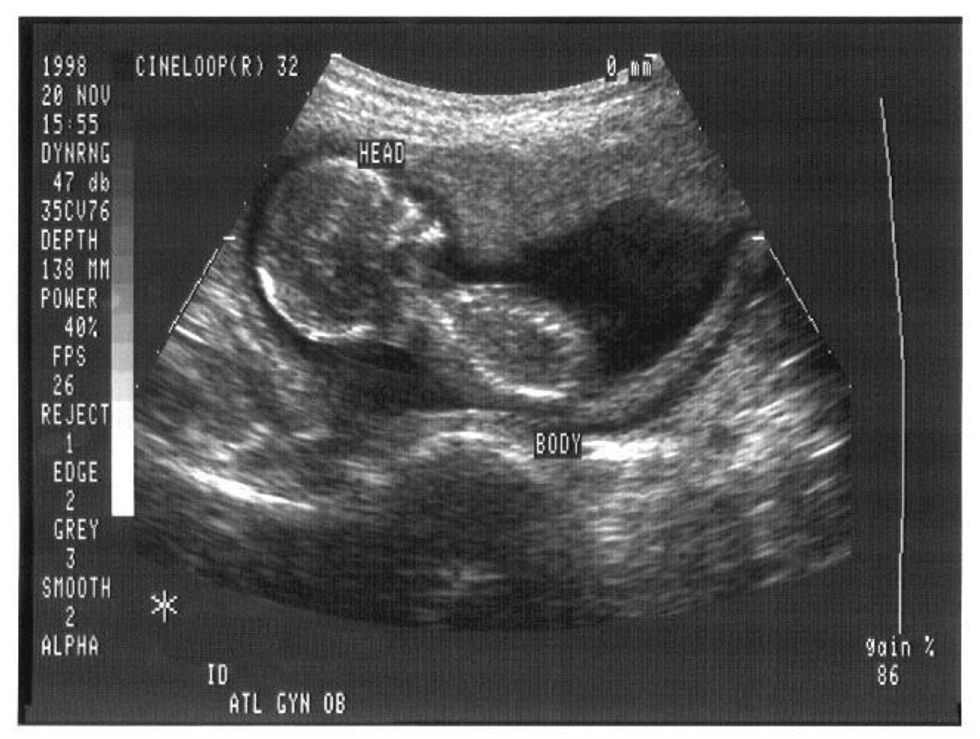

Abortion is a horrible thing, you are taking a human life, but you are taking a human life before it has a chance to become human. A baby cannot survive outside the womb until it's 24 weeks, and only has about a 40 to 50 percent of living, with extreme medical care. The fetus doesn't feel pain during the procedure, most doctors say that a fetus hasn't produced pain receptors and the parts of the brain that alerts pain until during third trimester. Most abortions are performed less then 12 weeks into the pregnancy. Woman believed to get it over with as quick as possible, because it is a horrible thing, but they made they choice.